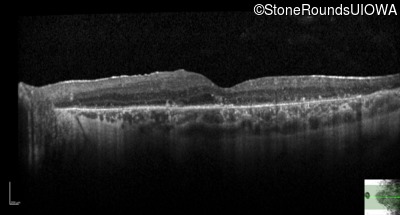

Optical Coherence Tomography - Right - 20/32 -1

Exemplar / OCT Stack

Optical Coherence Tomography - Left - 20/40 -1